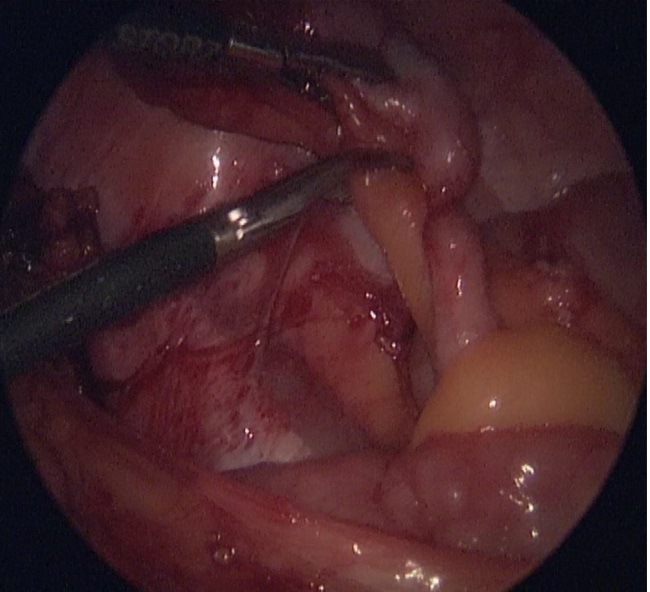

Через 6 месяцев выполнена лапароскопическая аппендэктомия в плановом порядке.

Рис 4 – интраоперационное фото – лапароскопическая аппендэктомия в плановом порядке

Рис 5 – интраоперационное фото – лапароскопическая аппендэктомия в плановом порядке

Данный случай иллюстрирует возможности лечения детей с осложненной формой острого аппендицита (аппендикулярный инфильтрат, оментит) с использованием консервативной терапии и последующей плановой лапароскопической аппендэктомией. В лечении девочки помимо хирургов принимали участие также анестезиологи-реаниматологи, педиатры, врач-гинеколог, клинический фармаколог, физиотерапевт.